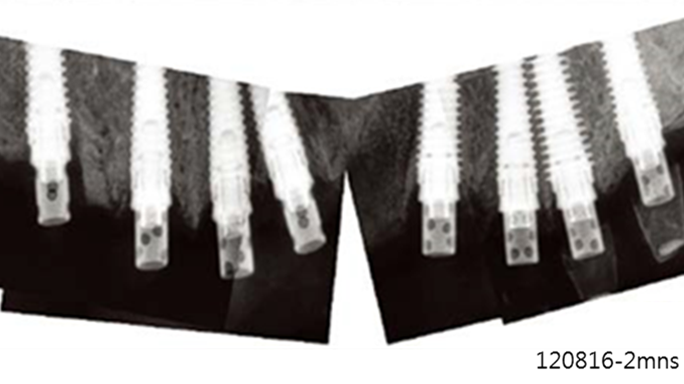

“AnyRidge shows excellent initial stability

& stable results after immediate loading in

upper fully edentulous case. ”

Clinical case: Extraction of all teeth in upper maxilla,

immediate implant placement, & provisionalization

- Courtesy of Dr. Iulian Filipov, Romania -

Keywords

AnyRidge, immediate placement, immediate provisionalization, maxillary fully edentulous case, initial stability, edentulous, Dr. Iulian Filipov, R2GATE, MEGA ISQ

Products:

AnyRidge implant system, Mega ISQ, R2GATE